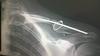

No nevím jak tohle nazvat – merkur? Dráty to asi nebudou…

0 0

•

Hezký řetízek! :-)

• Pedro404

To je dlaha, no. Do toho stačí trochu ťuknout a udělá to todle.